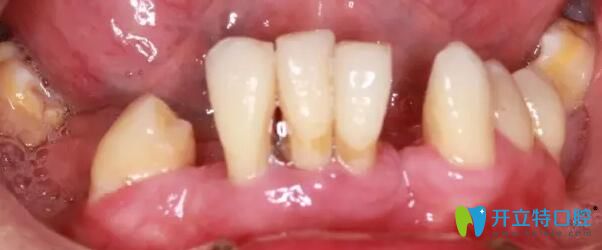

南通摩爾口腔牙齒種植前

(圖一)術(shù)前患者口腔狀況圖

患者王某35歲,在青少年時期患牙周炎,導致下頜部分牙齒缺失,殘留牙松動近十年,一吃飯就犯愁,非常痛苦,而且影響美觀。而他本人在外地上班,經(jīng)常需要接觸不同的人群,對形象要求特別高。前不久慕名尋找到南通摩爾口腔院長周文清幫他看牙。

術(shù)前全景片,下頜大部分牙齒缺失,殘留牙牙槽骨吸收明顯,從醫(yī)生的角度看,一個三十歲左右的青年人,牙病如此嚴重,實屬罕見。經(jīng)過了解,王先生從小害怕看牙,有牙齒問題遲遲未做治療,拖延病情至今。本次尋找周院長看牙,一是自己牙齒情況已經(jīng)嚴重影響到自己的正常生活,二是經(jīng)過多方打聽,相信周院長的技術(shù)一定可以幫助自己擺脫長期缺失牙的狀況。